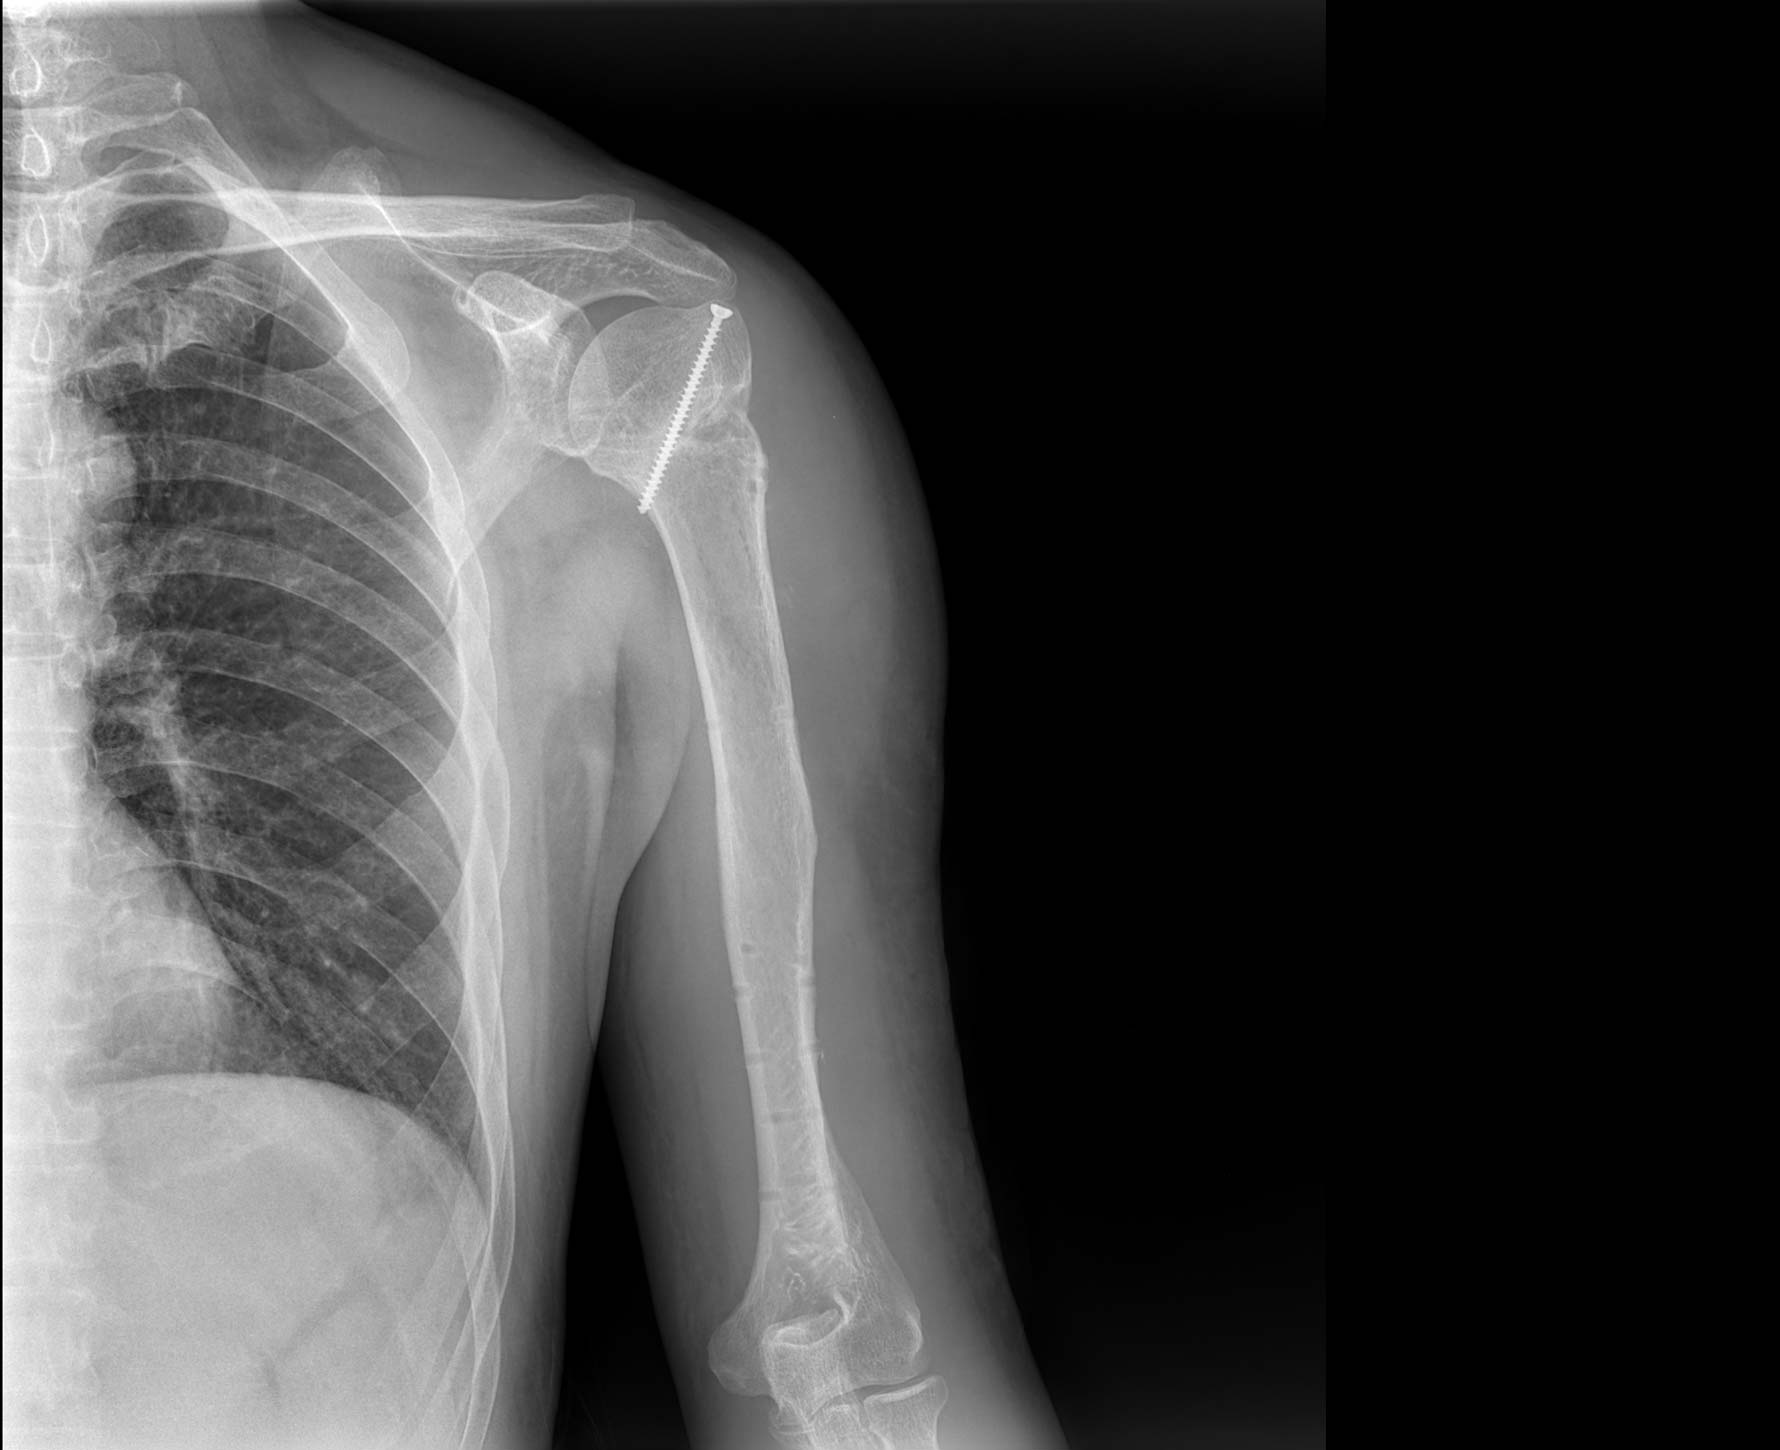

適用于全身各部位攝影

(常規攝影和特殊攝影)